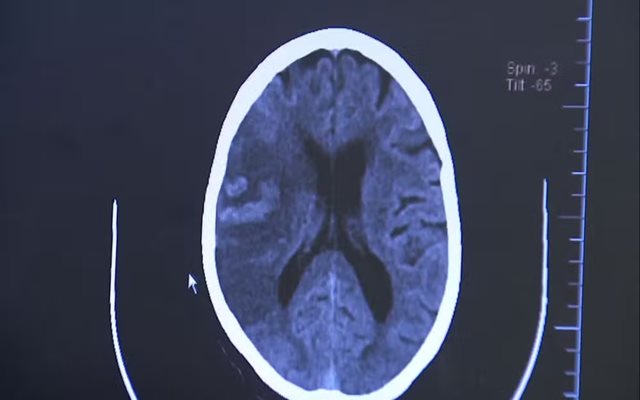

Tipos de AVC

Isquêmico (85% dos casos): ocorre quando há entupimento de um vaso sanguíneo que leva sangue ao cérebro. Está ligado à pressão alta e a doenças cardíacas, como a fibrilação atrial, que pode formar coágulos e bloquear artérias cerebrais.

Hemorrágico (15% dos casos): acontece quando há rompimento de um vaso, provocando sangramento no tecido cerebral. É menos comum, mas mais grave, com alto risco de sequelas e morte.